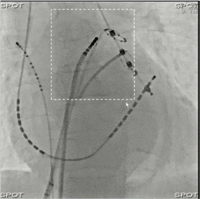

「スポット透視機能」は透視モニタ上でX線照射したい関心領域を指定し,その領域のみにX線照射されるようX線絞りが設定される。関心領域は画面中心でなくても良く,X線照射においてはどのように絞られていても適切なX線自動輝度制御を行うことで,絞込みによるX線照射量の増加を防ぐことができる。また,絞りのかけられた領域には,直前の全面透視の静止画像を表示し,画面全体の様子を想像できる(図1)。

図1 スポット透視の例